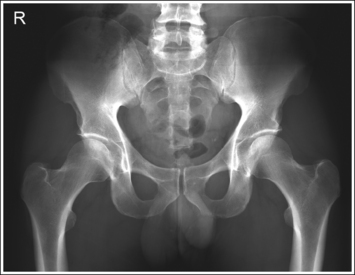

The pelvis demonstrates an AP projection. The ischial spines are aligned with the pelvic brim, the sacrum and coccyx are aligned with the symphysis pubis, and the ilia and obturator foramina are open and uniform in size and shape.

• Pelvic rotation. A nonrotated AP pelvis projection demonstrates symmetrical ilia and obturator foramina. Rotation is initially detected by evaluating the relationships of the ischial spines with the pelvic brim and of the sacrum and coccyx with the symphysis pubis. The ischial spines should be aligned with the pelvic brim, and the sacrum and coccyx should be in alignment with the symphysis pubis on a nonrotated pelvis. If the pelvis is rotated into a LPO position, the left ilium is wider than the right, the left obturator foramen is narrower than the right, the left ischial spine is demonstrated without pelvic brim superimposition, and the sacrum and coccyx are not aligned with the symphysis pubis but are rotated toward the right hip (see Image 16).

IMAGE 16

• If the patient was rotated into a right posterior oblique (RPO) position, the opposite is true. The right ilium is wider than the left, the right obturator foramen is narrower than the left, the right ischial spine is demonstrated without pelvic brim superimposition, and the sacrum and coccyx are rotated toward the left hip.

The femoral necks are demonstrated without foreshortening and the greater trochanters are in profile laterally, whereas the lesser trochanters are superimposed by the femoral necks.

• Accurate leg positioning. To demonstrate the femoral necks without foreshortening and the greater trochanters in profile on an AP pelvis projection, the patient's leg should be internally rotated until the feet are angled 15 to 20 degrees from vertical and the femoral epicondyles are positioned parallel with the imaging table (Figure 7-24; see Figure 7-21). Sandbags or tape may be needed to help maintain this internal leg rotation. An AP pelvis projection may not demonstrate the proximal femurs with exactly the same degree of internal rotation. How each proximal femur appears will depend on the degree of internal rotation placed on that leg.

• Poor leg positioning. The relationship of the patient's entire leg to the imaging table determines how the femoral necks and trochanters are shown on an AP pelvis projection. In general, when patients are relaxed, their legs and feet are externally (laterally) rotated. On external rotation, the femoral necks decline posteriorly (toward the table) and are foreshortened on an AP pelvis projection. Greater external rotation increases the posterior decline and foreshortening of the femoral necks. If the patient's legs are externally (laterally) rotated enough to position the feet at a 45-degree angle and an imaginary line connecting the femoral epicondyles at a 60- to 65-degree angle with the imaging table, the femoral necks are demonstrated on end and the lesser trochanters are demonstrated in profile (Figure 7-25; see Image 17). If the patient's legs are positioned with the feet placed vertically and an imaginary line connecting the femoral epicondyles at approximately a 15- to 20-degree angle with the imaging table, the lesser trochanter is demonstrated in partial profile and the femoral neck is only partially foreshortened (see Image 18).

IMAGE 17

IMAGE 18

The left obturator foramen is narrower than the right foramen, the left ischial spine is demonstrated without pelvic brim superimposition, and the sacrum and coccyx are rotated toward the right hip. The lesser trochanters are demonstrated medially and the femoral neck is foreshortened. The pelvis was rotated onto the left hip (LPO) and the legs were externally rotated.

Rotate the patient toward the right hip until the ASISs are positioned at equal distances from the imaging table and internally rotate the patient's legs until the feet are angled 15 to 20 degrees from vertical and the femoral epicondyles are positioned parallel with the imaging table, as shown in Figure 7-24.

The femoral necks are completely foreshortened and the lesser trochanters are demonstrated in profile. The patient's legs were externally rotated, with the patient's feet at a 45-degree angle and the femoral epicondyles positioned at a 25- to 30-degree angle with the imaging table, as shown in Figure 7-25.

Internally rotate the patient's legs until the feet are angled 15 to 20 degrees from vertical and the femoral epicondyles are positioned parallel with the imaging table, as shown in Figure 7-24.

The femoral necks are partially foreshortened, and the lesser trochanters are demonstrated in profile. The patient's legs were externally rotated, with the feet vertical and the femoral epicondyles at approximately a 15- to 20-degree angle with the imaging table.